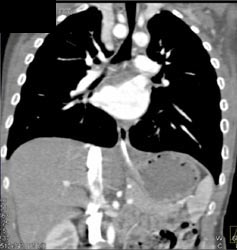

Airway Narrowing Due to Double Arch